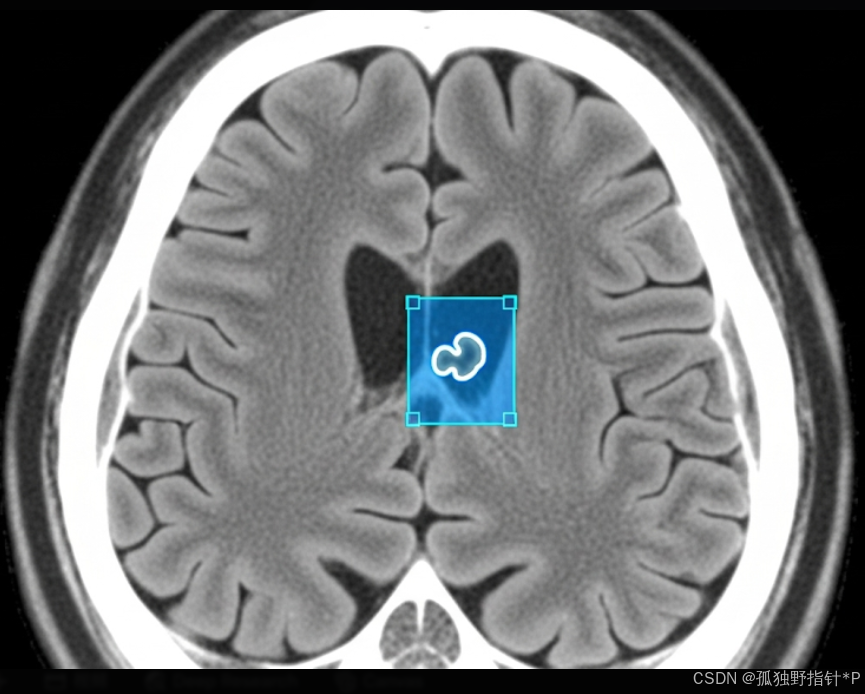

医疗影像分析: 在X光片、CT扫描、MRI图像中检测特定的肿瘤、病变或其他异常结构。通用模型可能不包含这些医学特征,通过微调,可以训练模型专注于识别这些特定的医学指标。